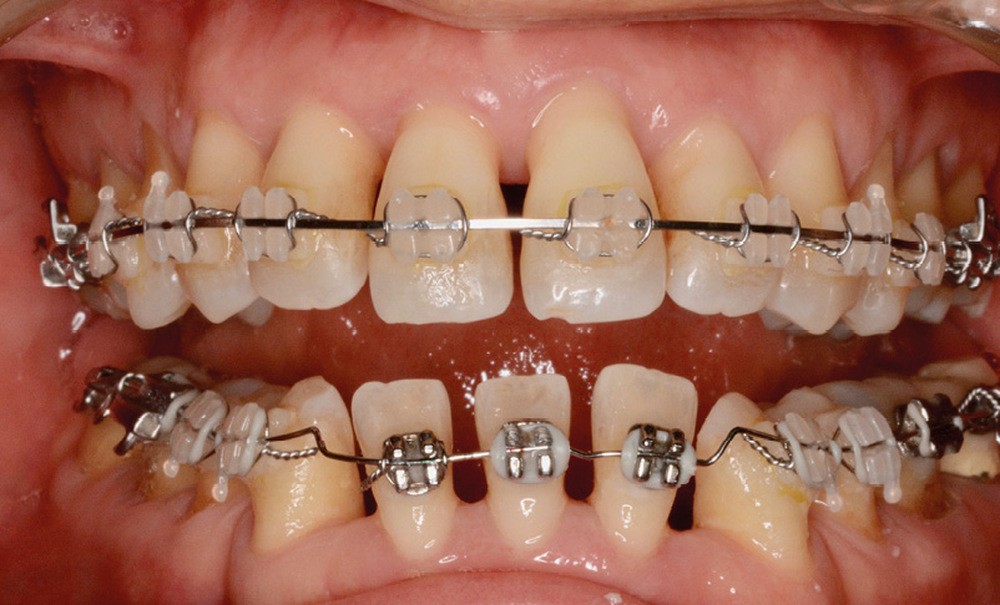

Un traitement en technique vestibulaire par appareillage multi-attaches .022 x .028 inch (prescription selon Roth) est entrepris, avec avulsion de prémolaires (15, 25, 34, 44).

La patiente ne supportant aucune cale occlusale, le collage de l’arcade mandibulaire est séquentiel afin de ne placer aucune attache en interférence occlusale. Le recul canin mandibulaire se fait grâce à des arcs sectionnels à boucle en Titane-Molybdène (TMA) .017 x .025 (fig. 10).

L’alignement et le nivellement maxillaires sont conduits en arc droit, et la mésialisation molaire réalisée en glissement, soutenue par des élastiques inter-arcades de classe III.

Le nivellement mandibulaire par ingresssion des incisives est mené via des arcs acier à la déformation avant de pouvoir recoller les brackets incisifs dans une position permettant de terminer le traitement en arc droit (fig. 11).